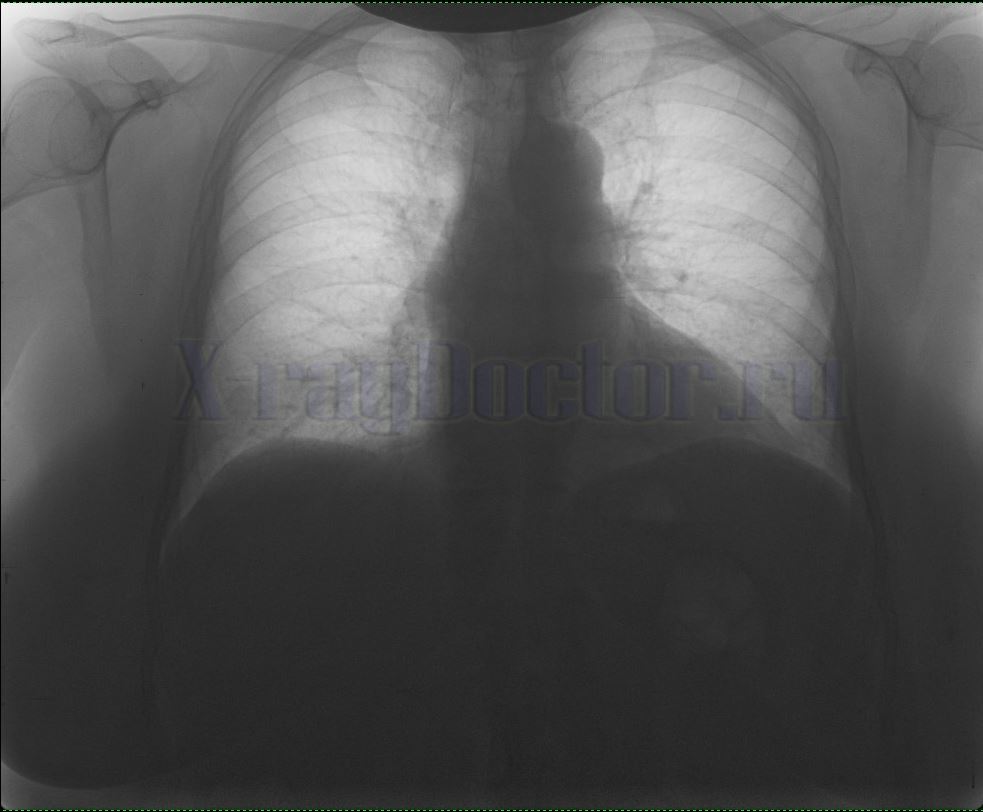

Снимок легких здорового человека выглядит типично:

- Легочные поля, расположенные с обеих сторон грудной клетки.

- Сердечная тень и грудина – в центре рентгенограммы.

- Ключица – в верхней части.

- Купола диафрагмы – снизу под легочными полями.

- Линейные тени ребер над проекцией легких.

На рисунке приведена нормальная рентгенограмма легких. Запомните ее вид. Если на снимке обнаружите дополнительные пятна, которые отличаются от вышеприведенного фото, скорее всего, такая картина будет отражать патологический процесс.